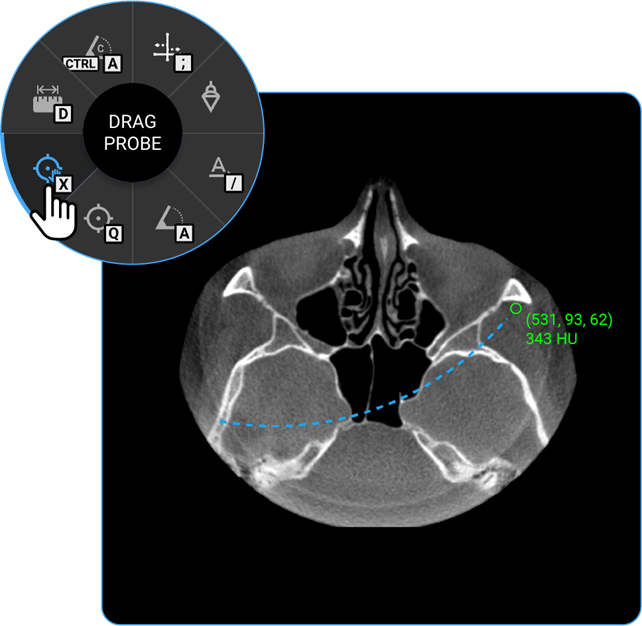

- Drag Probe: Click on the Drag Probe tool to move a probe point across the image and assess pixel values or other parameters dynamically.

- Probe: Select the Probe tool to analyse specific pixel values, providing information on intensity or density at a particular point.